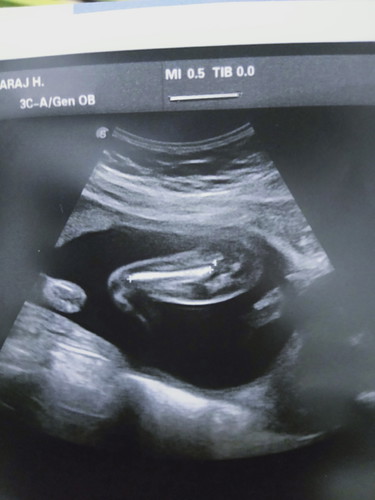

อายุครรภ์ได้ 19w 5d วันนี้ไปหาหมอมา หมอไม่อธิบายไรเลยสักคำ น่าบึ้งเราก้ไม่กล้าถาม อยากรุ้ว่ารุปที่ซาวด์มาคืออะไร แล้วน้ำหนักเด็กประมาน 318 กรัมรึป่าว

กระดูกต้นขาค่ะ หมอจะดูรอบหัว ท้อง ต้นขา เพื่อคำนวนน้ำหนักของทารกในครรภ์ และจะตรวจการเต้นของหัวใจว่าเหมาะสมปกติไหม ตรวจจับ ปอด กระเพราะอาหาร เป็นต้นค่ะ

ภาพกระดูกต้นขาน้องค่ะแม่ หมอจะวัดความยาวเพื่อดูว่าน้องโตสมอายุครรภ์เปล่า ถ้าหมอไม่พูดอะไรน่าจะปกติค่ะ